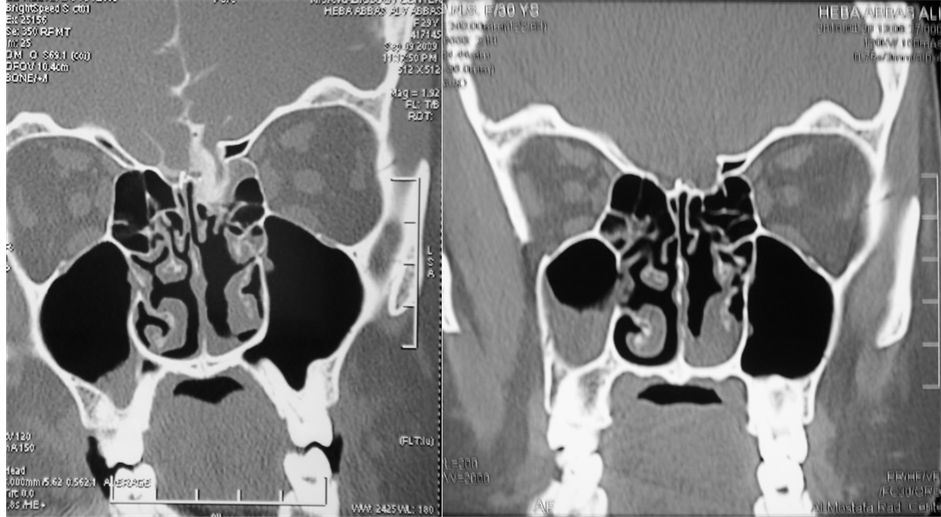

The site of the leak was localized preoperatively in the radiological examination in all cases (Table 1). No cases had multiple sites of leak in our series. A meningoencephalocele was found in 13 cases (48%) (Figure 2).

A delayed frontal mucocele occurred in a patient treated externally after 8 months necessitating reoperation. All patients had successful repair with no recurrences with follow up period of 6 - 60 months (mean = 30 months) (Figures 2-5).

Figure 5. (a) CT cisternography with metrizamide showing a left sided large skull base defect in the fovea ethmoidalis; (b) Follow up CT scan after 12 months showing successful repair.